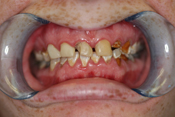

WORST TEETH Pictures from Warren Dentistry

This can happen to your teeth when proper Dental Hygiene is not practiced.

Patient 1